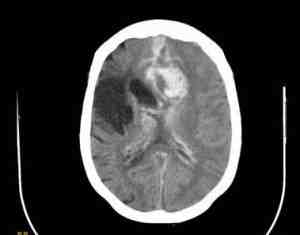

Afectación neurológica en paciente con anatomía vascular congénita

Introducción

Se desconoce la causa de la malformación

arteriovenosa cerebral (MAV). La afección ocurre cuando las arterias en

el cerebro se conectan directamente con las venas cercanas, sin tener

los vasos normales (capilares) entre ellas.

Las malformaciones arteriovenosas varían en tamaño y ubicación en el cerebro.

Una ruptura de una malformación

arteriovenosa ocurre debido a la presión y daño al tejido del vaso

sanguíneo. Esto permite que la sangre se escape hacia el cerebro o los

tejidos circundantes y reduce la circulación al cerebro.